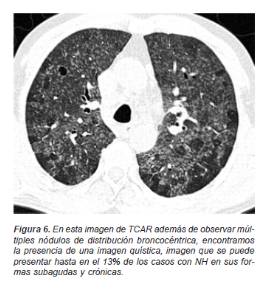

Así mismo se le considera otro tipo de alteración secundaria a la obstrucción bronquiolar parcial por infiltrados linfocíticos peribronquiolares a la presencia de lesiones quísticas en la TCAR que pueden llegar a presentarse hasta en el 13% (Figura 6) de los casos de acuerdo a la forma clínica de la enfermedad.